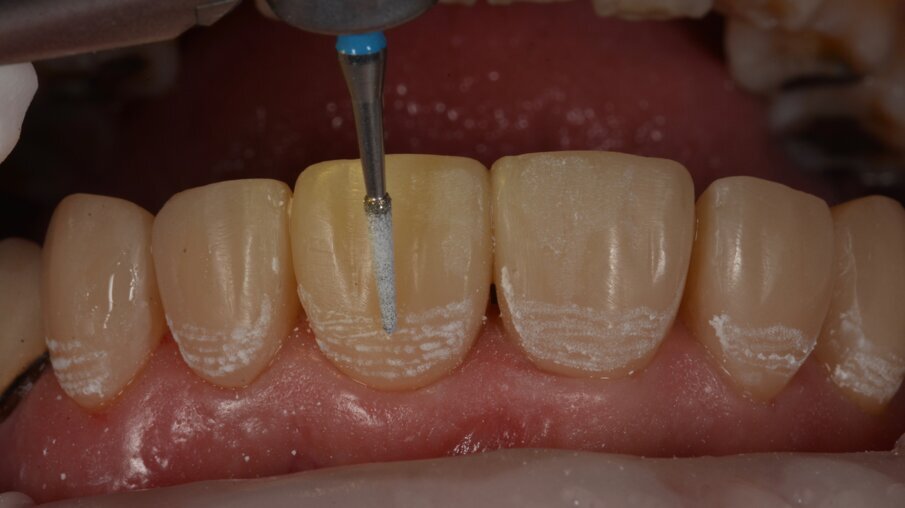

Dieptegroeven werden getrokken met een gekalibreerde boor door de mock-up om een uniforme dikte van het composiet te voorzien.